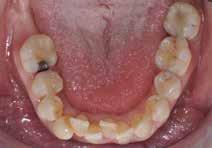

Den kliniske undersøgelse viser harmoniske ekstraorale sagittale forhold med skeletalt dybt bid (Fig. 1A, D). Hendes smil er alderssvarende med en eksponering på 8/10 af overkæbeincisiverne, mens smilets bredde er smalt med synlige mørke laterale rum (Fig. 1D). Underkæbeincisiverne er synlige under tale. Der ses neutrale okklusale forhold ved hjørnetænderne og neutrale pladsforhold i overkæben, men udtalt trangstilling i underkæben især lokaliseret i regio 1-1 (Fig. 1C).

Sliddet klassificeres som grad 2 (moderat tandslid) på de centrale incisiver i overkæbe og underkæbe. Det kan anses som patologisk, da det er atypisk for patientens alder, giver anledning til smerte/ubehag, og giver patienten et æstetisk problem. Der ses infraktioner af overkæbeincisiverne. Der ses endvidere en udtalt Spee-kurve i underkæben og ingen interincisal afstøtning på 2-2 med let ganepåbidning.

Den kliniske undersøgelse viser ingen symptomer fra muskler eller kæbeled. Ingen ledlyde ved åbne-/lukkebevægelse og ingen udsving ved åbne-/lukkebevægelse. Der er vertikalt overbid (VOB) 3-4 mm, horisontalt overbid (HOB) 1 mm, Angle kl. I med retroklination af såvel over- som underkæbeincisiver

(Fig. 6 A-D). Relativt flad Spee kurve. Ud fra TWES 2.0 graduering har pt. slid af 2. grad i over- og underkæbefront, dog har 1-1 slid af 3. grad. Incisiverne har skarpe incisalkanter med emaljefrakturer og emaljeinfraktioner (Fig. 6 C, D) samt udtalte dentinkonkaviteter incisalt (Fig. 6 E). Posteriort ses slid af 1.-2. grad, og der er mistanke om natlig bruksisme, selvom patienten ikke oplyser dette. Der er såvel attrition som erosion med cuppings på flere molarer samt hævede fyldninger med mindre frakturer (Fig. 6 F, G). Erosiv årsag kan ikke identificeres ud fra kostanamnese. Der ses tydelige slidfacetter i hele tandsættet generelt. Patienten har perfekt mundhygiejne, ingen caries, slimhindeforandringer eller patologiske pocher.